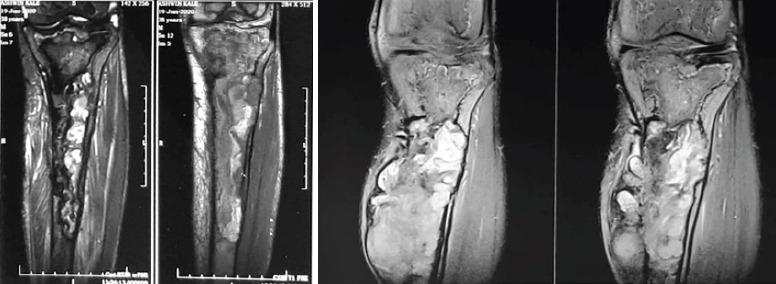

A 38-year-old man presented to our outpatient department with a solitary, painless soft-tissue swelling of the left proximal tibia noticed 6 months back, which has gradually progressed to a present size of 9x5 cm over a period of 6 months. General physical examination revealed moderate splenomegaly. Radiographs showed an osteolytic lesion in the left proximal tibia without cortical erosion. Radiographs for skeletal survey revealed similar osteolytic lesions elsewhere. Hematological investigations revealed thrombocytopenia. A serum protein electrophoresis was found to be normal and the urine was negative for myeloma proteins. Blood workup for endocrine abnormalities was within normal limits. MRI of the lesion suggests bone infarct. Biopsy from the lesion showed a giant binucleate storage cell filled with glucocerebrosides suggestive of Gaucher's disease. The diagnosis was confirmed by elevated plasma levels of glucocerebrosidases.

一名38岁男性因6个月前发现左胫骨近端有一个孤立的、无痛性软组织肿胀前来我院门诊就诊,在6个月内逐渐发展至目前9×5厘米大小。全身体格检查发现中度脾肿大。X线片显示左胫骨近端有一个溶骨性病变,无皮质侵蚀。骨骼检查的X线片显示其他部位也有类似的溶骨性病变。血液学检查发现血小板减少。血清蛋白电泳正常,尿液中骨髓瘤蛋白检测为阴性。内分泌异常的血液检查结果在正常范围内。病变的磁共振成像提示骨梗死。病变活检显示一个充满葡萄糖脑苷脂的巨大双核贮积细胞,提示戈谢病。血浆葡萄糖脑苷脂酶水平升高证实了诊断。